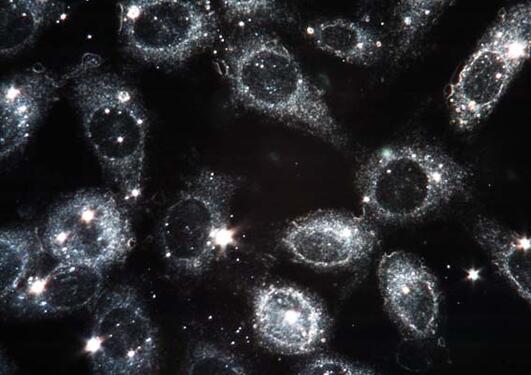

The laboratory-based testing methods include chemical analysis, physico-chemical characterization, biomechanical characterization and simulation, radiostereometric analysis, cell culture studies as well as analyses of retrieved materials and tissue, which establish the link to clinical research and registry studies.